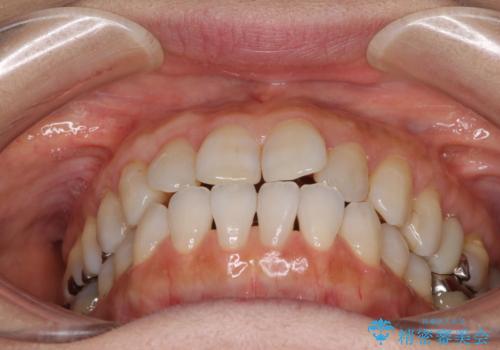

前歯の突出感と上下の隙間 インビザラインによる矯正治療

- 前歯の上下スペースと前歯の隙間を気にして来院された患者様です。

インビザラインにより上下の前歯の隙間を閉じながら、IPRを用いて口元の突出感を合わせて改善していくこととしました。

上下の隙間に舌が入り込むことが、すきっ歯やオープンバイトの原因であったため、舌の筋肉のトレーニングも並行して行い、後戻りの抑制を図りました。